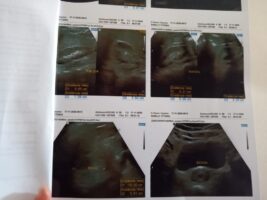

Veja os exames da adolescente: